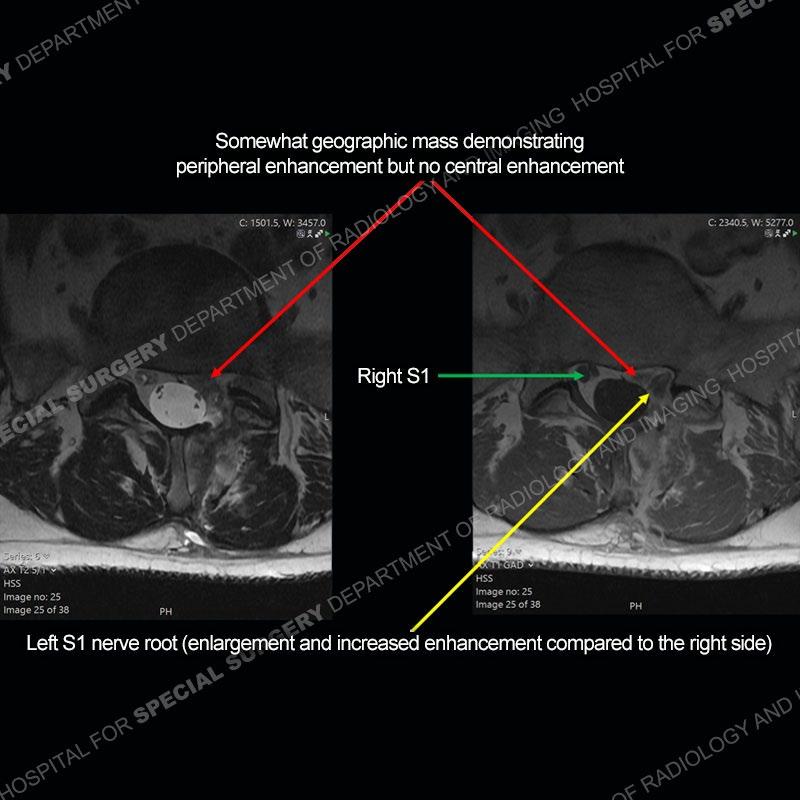

Post operative changes are seen on the left side at L5-S1 where there is near complete removal of the left sided L5 lamina, partial resection of the left L5-S1 facet joint, and resection of the left sided ligamentum flavum. In the anterolateral epidural space about the subarticular recess is a mass that demonstrates similar T1 and T2 signal characteristics to the adjacent degenerated disc. There is enhancement about the periphery of the mass, but the majority of this somewhat geographic or polyploid mass demonstrates no enhancement. The mass exerts prominent mass effect on the left S1 axillary sleeve/proximal nerve root. The left S1 nerve root shows enlargement and increased enhancement as compared to the contralateral right side.

Not as much of a diagnostic dilemma as some other cases but more so just a very nice example of what can be a difficult assessment at times. The evaluation of granulation tissue/scar/epidural fibrosis vs. disc herniation particularly in the earlier post operative period can be very difficult. Clues that can assist in identifying a disc herniation are a more geographic or polypoid nature to the mass, signal characteristics similar to the adjacent degenerated disc, mass effect upon the thecal sac/adjacent neural structures, and a typical enhancement pattern. As the disc material is avascular, as long as imaging is performed in a relatively rapid fashion after contrast administration (within 20-30 minutes), the granulation tissue around the disc will enhance but the disc material itself will not. If there is a marked delay between contrast administration and imaging, there may be diffusion of contrast into the disc making the assessment very difficult. The marked utility of contrast to help delineate disc vs. scar has led to our institution employing contrast fairly uniformly within the first two years following surgery.